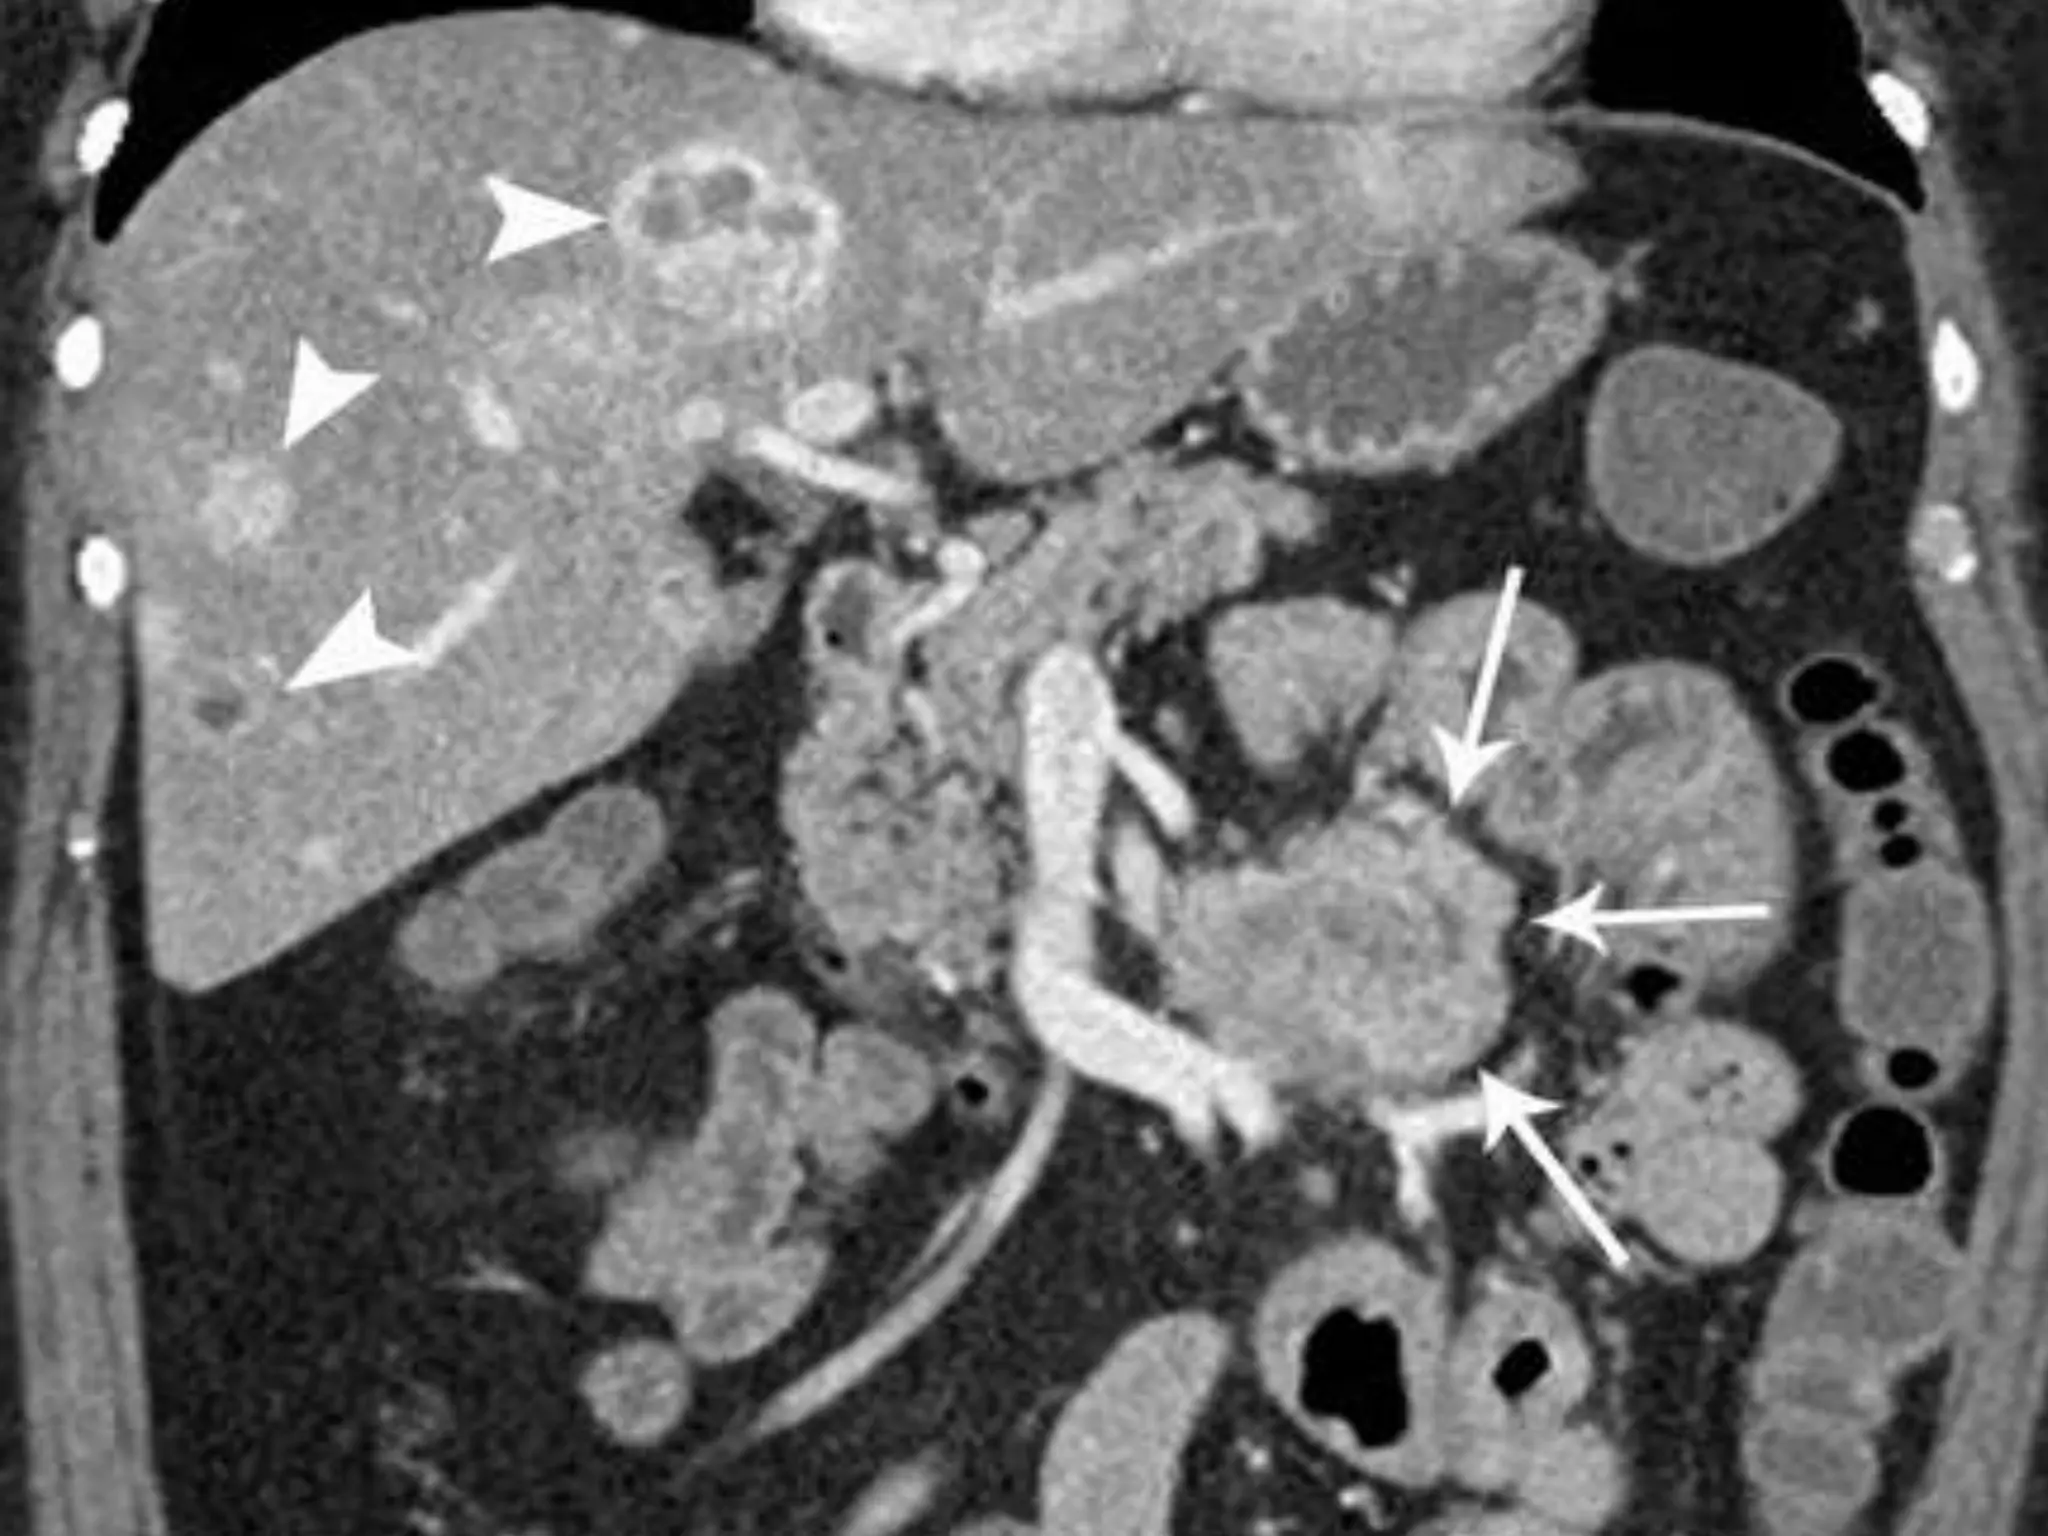

• #11 hypervascular enhanced intraluminal mass

• #12 Figure 15d.  Varied appearances of small bowel carcinoid tumors. (a) CT enterogram demonstrates a submucosal carcinoid tumor (arrows) within a Meckel diverticulum. (b) CT enterogram obtained in a different patient demonstrates a carcinoid tumor (arrow) within the wall of the ileum. (c) CT enterogram obtained in a third patient shows mesenteric metastases from an ileal carcinoid tumor. Note the enhancing, star-shaped mesenteric nodule (arrowhead), with stranding of the mesentery and thickening of the adjacent small bowel wall (arrows). The segmental wall thickening may indicate either a carcinoid carpet lesion or segmental edema. (d) Coronal reformatted CT enterographic image obtained in a fourth patient demonstrates a mesenteric carcinoid tumor (arrows) with hypervascular liver metastases (arrowheads).